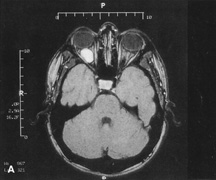

Fig. 14. A,B. Large intraorbital lymphangioma causing proptosis and optic nerve compression in a 2-year-old child. C. View of the left orbit from above after removal of the frontal bone flap, including the supraorbital rim and orbital roof. An extensive exposure of the entire superior and lateral orbit is afforded. The levator and superior rectus complex is being retracted laterally with a muscle hook, whereas the Freer elevator retracts the superior oblique muscle medially. The frontal nerve can be seen running from posterior to anterior over the superior orbit. The orbital mass is exposed in this fashion. D. The fronto-orbital bone flap is wired back in place after completion of the procedure. E. Postoperative appearance of the patient. F. The postoperative CT scan shows complete removal of the lymphangioma. This large and diffuse lesion would have been difficult to remove with any other approach.